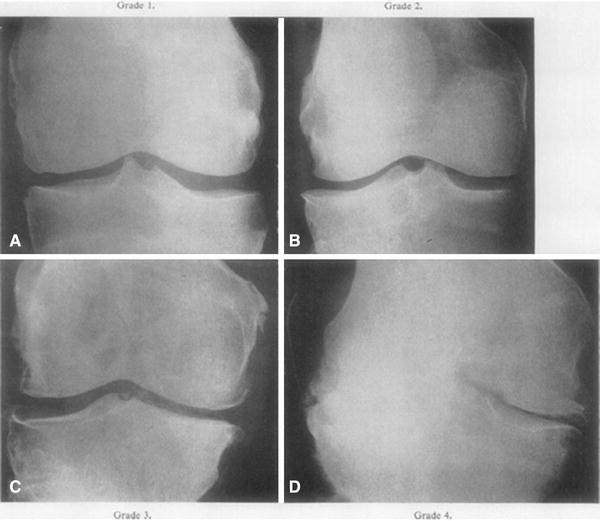

Grade를 각각 자세히 보게되면

0은 정상

1은 JSN(joint space narrowing)나 작은 골극이 생길수 있고 (fibrillation, disruption)

2부터는 JSN 가능성이 1보다 높아지고, 명확한 골극이 관찰됩니다.

3부터는 여러 골극과, 중등도 JSN와, 뼈의 변형, 연골하골 경화의 관찰이 있을 수 있습니다.

마지막 단계인 4의 경우 큰 골극과, 매우 명확한 JSN, 심한 연골하골 경화, 뼈의 심한 변형 등이 있을 수 있습니다.

아래 여러 사진을 보면서 한번더 확인해보면 0에서 4로가면서 관절간격도 좁아지며, 골극과, 뼈의 변형이 더 심해지는 것을 알 수 있습니다.